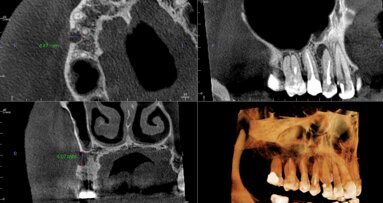

Prawidłowe trójwymiarowe pozycjonowanie implantu jest jednym z kluczowych czynników determinujących przewidywalne leczenie implantoprotetyczne. ...

Wykorzystując postęp w technologii druku 3D, badacze z Uniwersytetu Technicznego w Atenach przy współpracy z Katedrą Diagnostyki Jamy Ustnej i ...